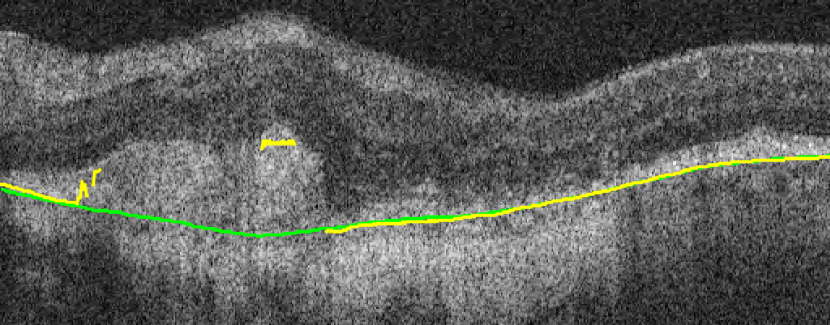

(a) Before TPS

(b) After TPS

A representative example of the influence of the curvature term is shown in Fig. 17. The proposed method with the help of the curvature term correctly finds the BM as opposed to Proposed w/o w/o TPS. The associated uncertainty is also adequately higher, signaling the lower confidence of the BM position estimate in this region. In contrast, the absence of leads to a poor uncertainty estimation in some incorrect segmentation regions.

(a)

(b)